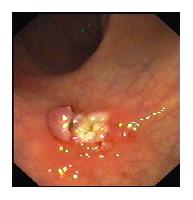

(四)、内镜下胃、肠道息肉切除术

胃、肠道息肉是重要的癌前病变,胃镜、肠镜检查一旦发现有胃、肠道息肉,就应该切除;否则就有癌变的可能。在胃镜或肠镜监视下行息肉电凝切术,是治疗息肉的最佳办法,创伤小,效果好。消化科拥有先进的德国爱尔博(ERBE)高频电凝切仪,配合电子胃镜、肠镜,行息肉电凝切术,效果良好。

肠道息肉切除术后